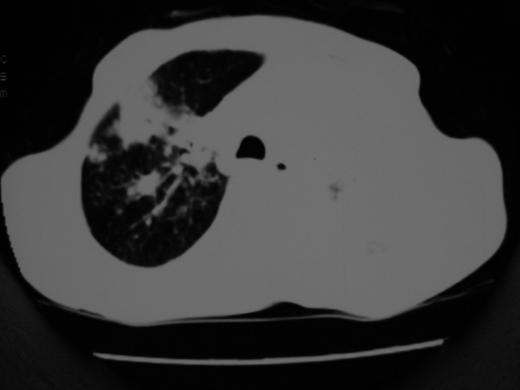

男69岁,年前胸片示肺感染治疗近一月今复查无明显好转,血象正常

双肺内不规则斑点状 片状及结节密实影,部分灶周见索条样影及\"树芽征\",左肺上叶实变,内见充气支气管影及斑状钙化,左侧少量胸腔积液,考虑1)双肺结核2)左侧胸腔积液

右肺多发片絮状结节状及时条索状影,左上肺实变,内可见虫蚀样空洞及支气管气象,左下肺片状及球形病灶,及胸腔积液征象,双肺病灶内多发钙化影,结合病史,考虑双肺继发型肺结核,左胸腔积液

右肺多发片絮状结节状及时条索状影,左上肺实变,内可见虫蚀样空洞及支气管气象,左下肺片状及球形病灶,及胸腔积液征象,双肺病灶内多发钙化影,上纵隔向左侧移位,结合病史,考虑双肺继发型肺结核,左胸腔积液。

右肺多发片絮状、结节状及条索状影,左上肺实变,内可见虫蚀样空洞及支气管气象,左下肺片状及球形病灶,有胸腔积液征象,双肺病灶内多发钙化影,上纵隔向左侧移位,结合病史,考虑双肺继发型肺结核,左胸腔积液。 建议结合ppd检查或纤支镜检查!